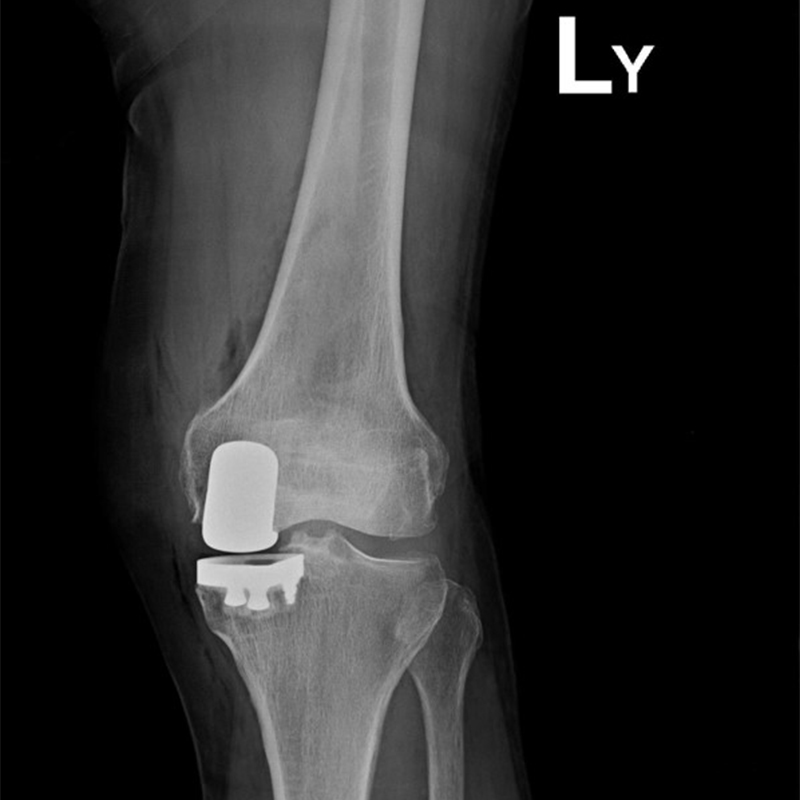

傳統部分膝置換 首頁 案例分享 膝關節手術 傳統部分膝置換 殷女士 65歲 術前 術後 張女士 71歲 術前 術後 蔡女士 74歲 術前 術後 張女士71歲 術前 術後 翁女士70歲 術前 術後 劉女士 80歲 術前 術後